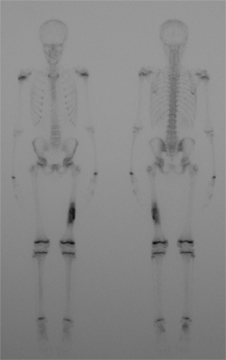

Une étude publiée en 2004, ayant exploré la vascularisation

des membres inférieurs par scintigraphie osseuse au Technetium

99m, ne retrouve pas de différence de vascularisation

en cas de douleur de croissance.